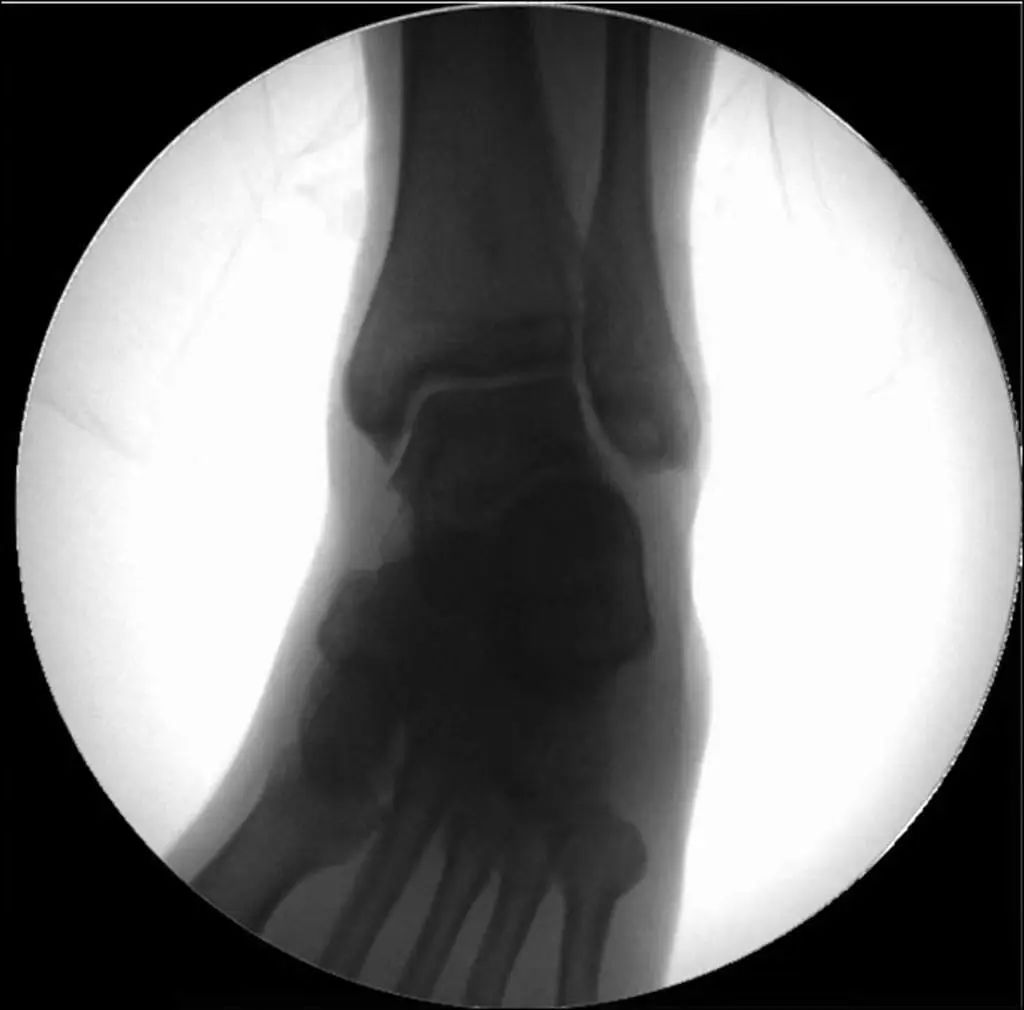

Рентгенодиагностика. Стандартная визуализирующая оценка голеностопного сустава должна включать 3 фазы: переднезаднюю (рис. 8), точку голеностопного сустава (внутренняя ротация 15°) (рис. 9) и боковую (рис. 10).

Рисунок 8 Переднее и заднее положение

Рисунок 9. Точки голеностопного сустава (15° внутренней ротации)

Рисунок 10 Боковое положение